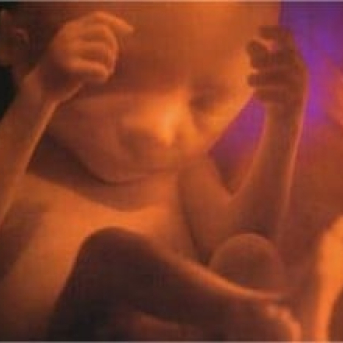

Com 5 meses o bebê está na sua fase de maior agitação. Mexe constantemente, principalmente no período noturno. Já mede em torno de 80 cm e pesa em média 700 gramas. Mesmo já totalmente formado e desenvolvido, não possui a aparência que nascerá, pois tem a pele muito fina, avermelhada e enrugada. Aparência essa que se modificará nas próximas semanas.